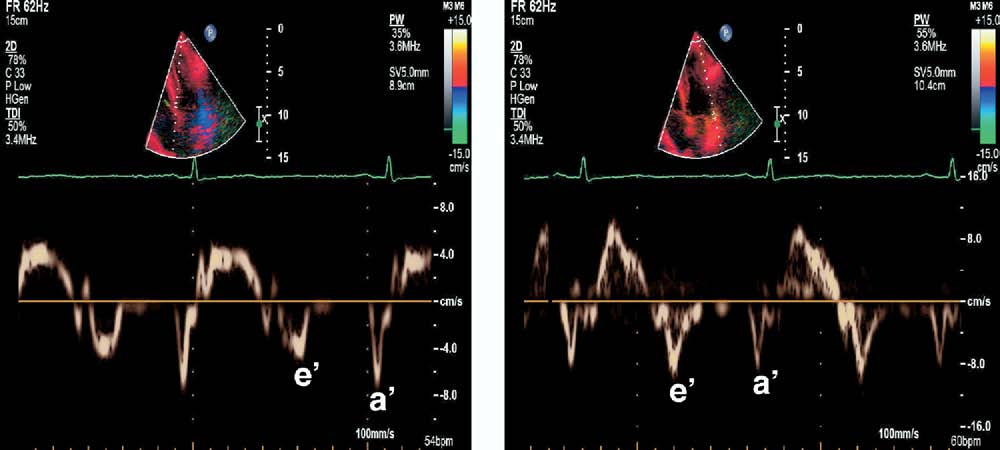

缩窄性心包炎患者超声心动图检查:二尖瓣环舒张早期速度(e′),间隔侧的舒张早期速度相对正常甚至增大(左图)高于游离壁(右侧)

缩窄性心包炎患者通常间隔侧e’增加(瓣环反转现象),主要是因为心包侧壁粘连而间隔瓣环的纵向运动未受影响所致(表现为左心室侧向及前后向的舒张位移受到限制,而长轴上的伸展代偿性增强)。

这种情况下,侧壁e’速度较室间隔e’速度低,E/e’比值与LV充盈压呈反相关或与瓣环运动相矛盾。